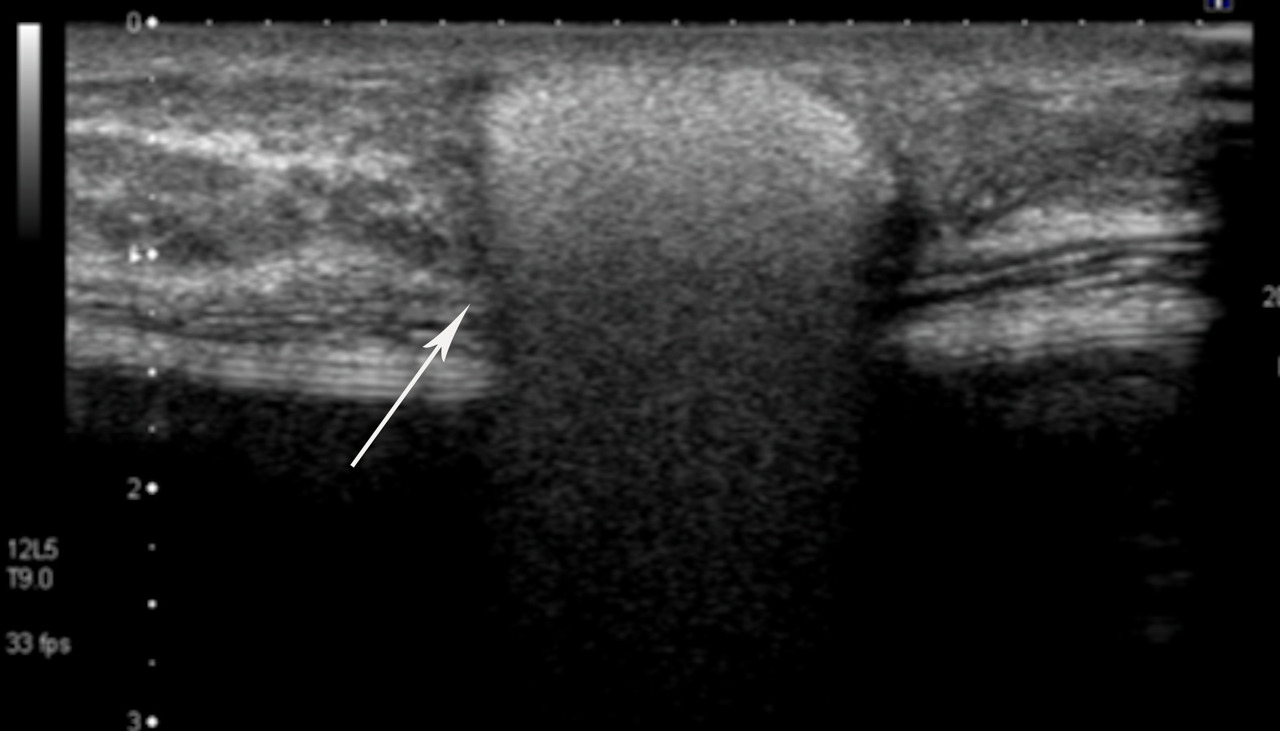

• extracapsulaire (fig. 3 et 4), contenu hétérogène avec échos internes et perte du contour régulier de la paroi à l’échographie. Diagnostic confirmé par l’IRM mammaire avec séquences dédiées silicone, qui montre l’incontinence de la prothèse (paroi irrégulière) et des dépôts de silicone rétro- ou périprothétiques. Des ganglions chargés en silicone peuvent être visibles.